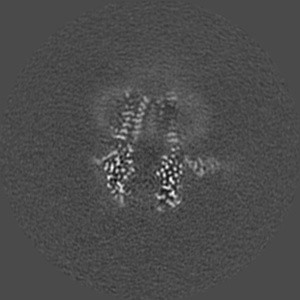

Cryo-EM structure of human full-length beta3delta GABA(A)R in complex with nanobody Nb25

Single-particle2.9 Å

Sample: Human full-length beta3delta GABA(A)R in complex with Nanobody Nb25